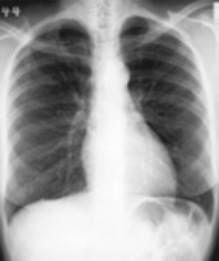

Dit is het meest uitgevoerde onderzoek op de dienst radiologie. Een thoraxfoto kan om veel redenen worden aangevraagd.

Er zijn in princiepe twee manieren om een thorax opname te maken:

De

staande opname waar meestal een face en een profiel opname wordt

genomen |

liggende opname bij een patiënt die niet kan staan, normaal enkel

face opname tenzij anders aangevraagd |